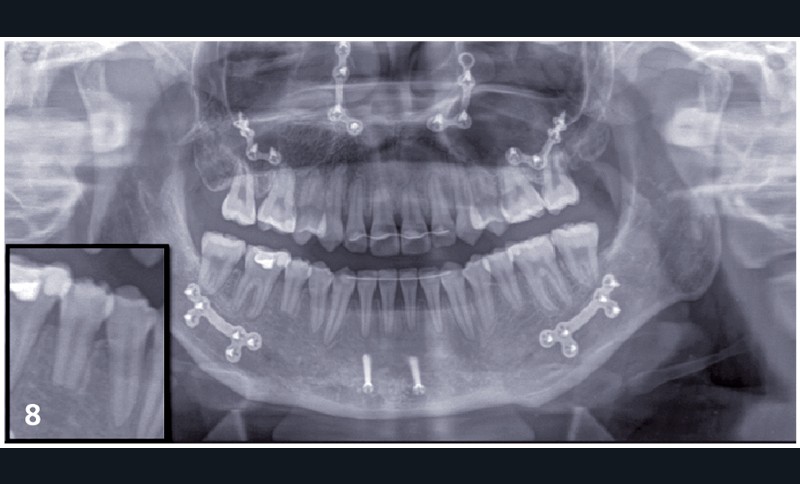

Sylvie se présente à l’âge de 15 ans avec une classe III squelettique (ANB -7,6°) d’origine maxillaire et mandibulaire sur un schéma facial à tendance hyperdivergent (FMA 31°) (fig. 1).

La classe III d’Angle et l’occlusion inversée s’accompagnent de signes de compensations alvéolo-dentaires : vestibuloversion des incisives supérieures (I/SN 114°) et linguoversion des incisives inférieures (IMPA 86°). L’encombrement à l’arcade maxillaire est important, souligné par des canines en infra-mésio-vestibulo-position.

Le choix du plan de traitement s’est porté sur un traitement chirurgico-orthodontique avec réalisation d’une classe II thérapeutique afin de limiter les déplacements dentaires à l’arcade mandibulaire suite au dépistage de rhizalyses idiopathiques sur les prémolaires inférieures (fig. 3) et de l’absence d’encombrement.